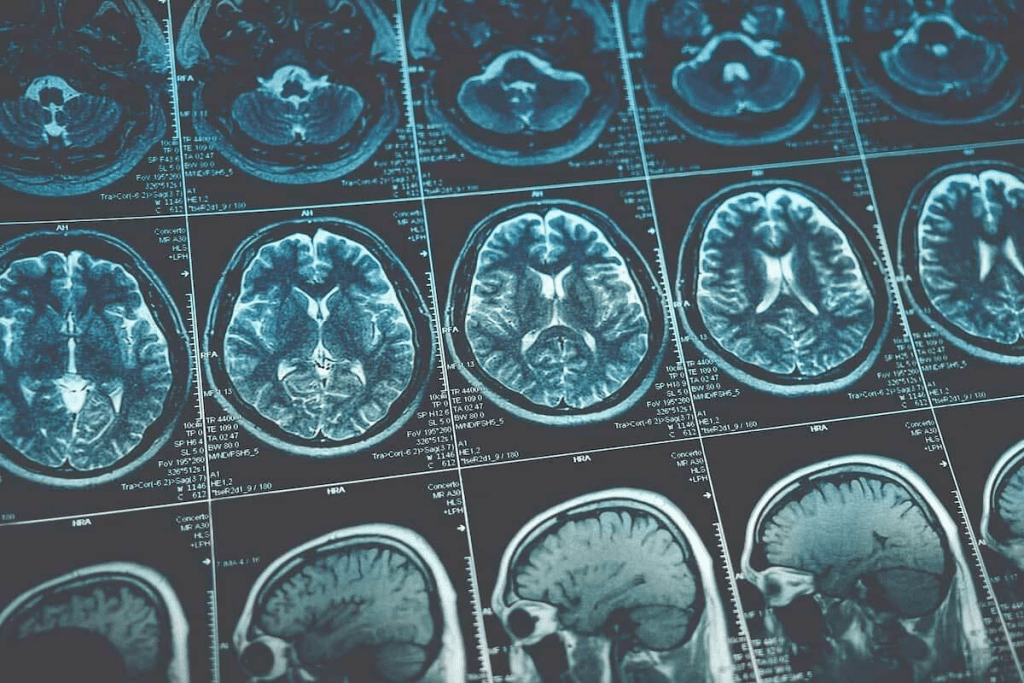

Medical imaging has changed how we find and understand small brain tumors. It helps doctors give the best care. We use MRI images to spot tiny changes in brain tissue. This helps us find both harmless and dangerous growths.

- MRI images help identify subtle changes in brain tissue, supporting the detection of benign and malignant growths.

Learning about MRI for brain tumor detection is key to good diagnosis and treatment plans. MRI is the top choice for finding brain tumors. It shows detailed images and looks at tumors from many angles.

MRI uses strong magnetic fields and radio waves to see brain tissue. It makes detailed pictures of brain structures. This helps spot even small changes in tissue, which is important for early detection.

We use MRI sequences like T1-weighted and T2-weighted images. T1-weighted images show clear anatomy. T2-weighted images are better at showing tissue changes.